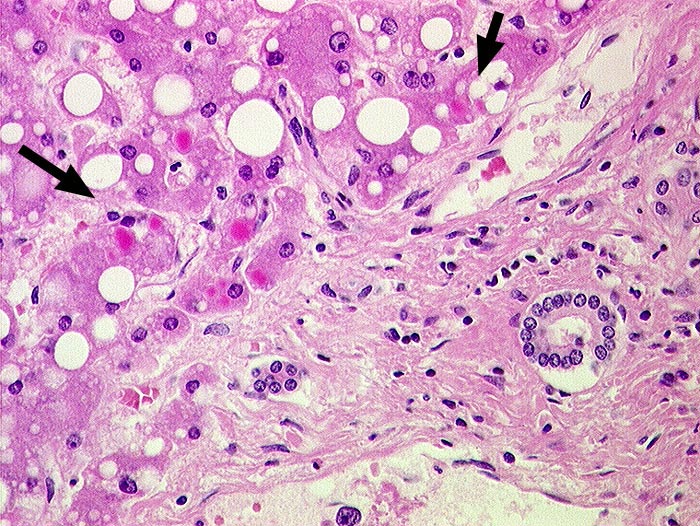

Leber bei Alpha-1-Antitrypsinmangel

Befund

Pathologischer Befund